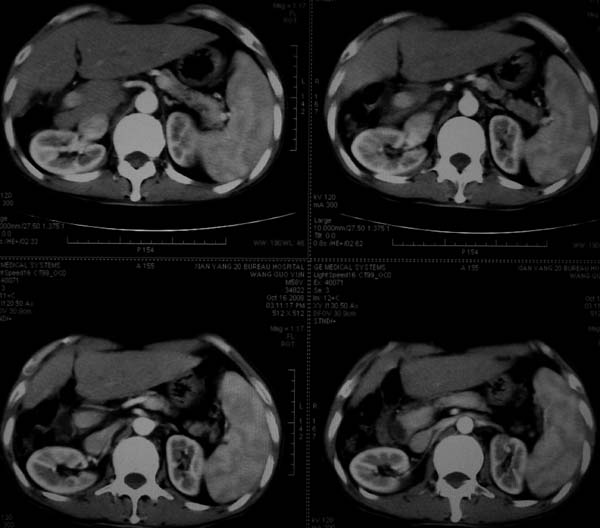

标题: CT16292:男,53岁,上腹部不适2月,B超发现肝内占位病变。 [打印本页]

标题: CT16292:男,53岁,上腹部不适2月,B超发现肝内占位病变。

符合肝ca增强,\"快进快出\";肝叶比例失常,右叶萎缩,肝裂增宽,脾大,肝硬化可能.

支持结节型肝癌。肝硬化脾大,病人是不是做过手术。

肝脏体积变小,肝裂增宽,分布异常,肝尾叶增大,脾肿大,考虑肝硬化可能性大,右肝病灶呈现早期充盈,延迟强化考虑肝内胆管细胞癌可能,不除外血管瘤

肝硬、脾大,右肾在稍息,考虑结节型肝癌可能,不排除血管瘤。

支持 结节型肝癌;肝硬化、脾大。

肝硬化,多结节肝癌。比较典型的表现了。

肝叶比例失调,左叶增大,肝裂增宽,脾脏增大,门脉增宽,肝右叶包膜下多发结节样阴影,增强虽说强化幅度不大,但还是符合快进快出特点;考虑肝硬化、脾大、结节型肝癌。胆管细胞癌多有延时强化、肝包膜凹陷征、周围胆管扩张等特点,本例明显不符;故不考虑。

支持结节型肝癌 肝硬化 脾大